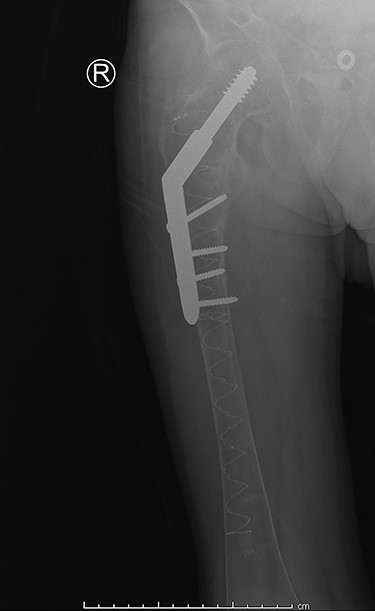

The patient was haemodynamically stable at presentation. He complained about pain in his right hip and was not able to move his right leg due to the pain. The patient was previously diagnosed with the renal Fanconi syndrome and had a previous collum femoris fracture on the left side. Conventional imaging revealed a subtrochanteric femoral fracture (Figs 1 and 2). Furthermore, contralaterally placed cannulated collum femoris screws and a severely decreased bone quality was found. No other traumatic injuries were present. Biochemical analysis showed a hypokalaemia of 3.0 mmol/l (3.5–5.0 mmol/l) and a mild hyponatraemia of 134 mmol/l (135–145 mmol/l). These findings can be related to the Fanconi syndrome.

Anterior-posterior view: right-sided subtrochanteric femoral fracture, left-sided collum femoris screws.